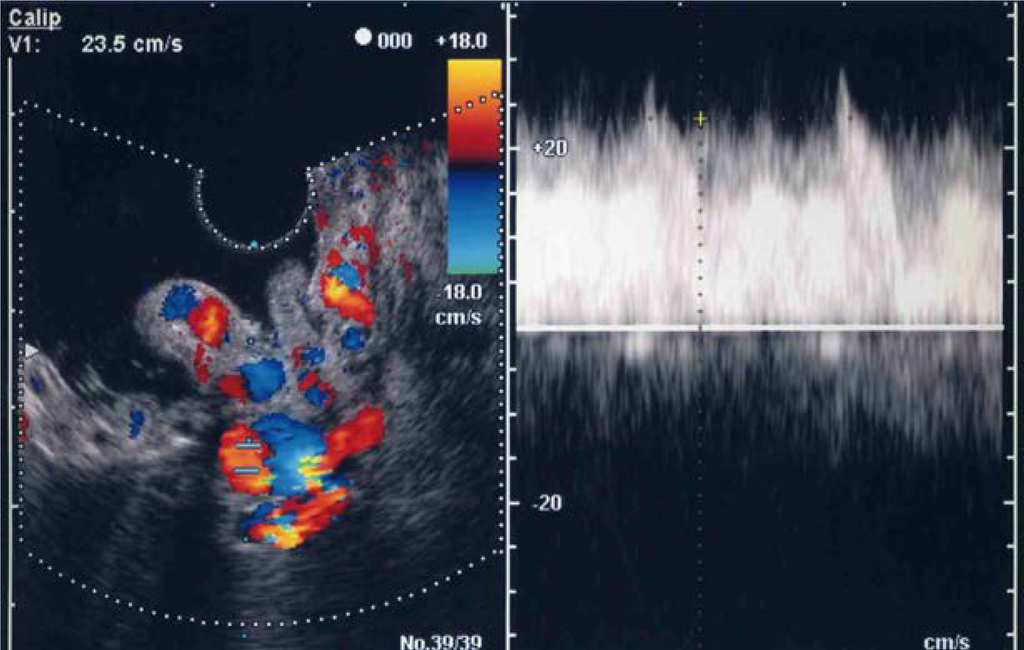

Using ECDUS color flow imaging, gastric varices were delineated in all 16 patients. FFT analysis of variceal blood flow showed a continuous wave in all 16 patients, with flow velocities in the gastric varices ranging between 8.6 and 28.6 cm/s (mean 17.1 ± 4.9 cm/s). Figure 3 shows an electronic radial-type ECDUS image of large, coil-shaped gastric varices located between the fundus and the curvatura ventriculi major of the gastric body, which flows as a continuous wave. Endoscopic findings showed enlarged tortuous, erosion-positive gastric varices in a round fundal region with the pancreatic cancer (Figure 4a). In this case, ECDUS demonstrated clearly gastric variceal color flow images of the round fundal region at the center that expand to the curvatura ventriculi major of the gastric body (Figure 4b). All 16 cases diagnosed as gastric varices secondary to splenic vein occlusion showed similar specific findings on ECDUS color flow images. The ECDUS color flow images of gastric variceal flow depicted specific findings of gastric varices secondary to splenic vein occlusion at the round fundal region at the center, with varices expanding to the curvatura ventriculi major of the gastric body.

Figure 3.

Endoscopic color Doppler ultrasonography showing a color flow image of gastric varices due to splenic vein occlusion that flow as a continuous wave.